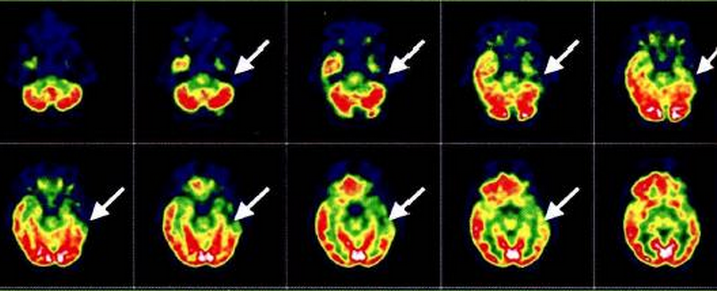

Рисунок 3. ПЭТ при эпилепсии. Эпилептогенный очаг в виде зоны гипометаболизма в правой височной доле (стрелки).

В клинической практике, наиболее часто, ПЭТ применяется с использованием флуорин-8-флуоро-2-дезокси-D-глюкозы (18-фтордезоксиглюкозы). Эпилептогенная зона характеризуется гипометаболизмом в межприступном периоде и гиперметаболизмом во время приступа.

В норме, в мозге взрослого человека происходит высокий захват ФДГ корой полушарий и мозжечка, а также умеренный захват в белом веществе. Захват ФДГ у детей варьируется в зависимости от возраста. Младенцы, как правило, показывают распространенную низкую метаболическую деятельность. После достижения 4-х месячного возраста происходит резкое увеличение метаболизма глюкозы и достигает своего пика около 4-х летнего возраста, несколько снижаясь в дальнейшем, по мере увеличения возраста. По мере старения, метаболизм, в норме, снижается в латеральных и медиальных отделах лобной коры, а также в передних отделах поясничной извилины. Патологически измененные регионы характеризуются увеличением, снижением или отсутствием метаболической активности. Полуколичественные анализы помогают обнаружить локальные или глобальные аномалии, незаметные при обычной нейровизуализации. Полуколичественные анализы включают сравнение захвата ФДГ в регионе интереса с общей картиной метаболизма. Они могут быть выполнены вручную или с помощью специальных программ. Возможна интеграция ФДГ-ПЭТ и МРТ, что повышает структурную и функциональную информативность. Количественный анализ (абсолютный метаболизм глюкозы) требует забор крови (артериальной) с динамическим измерением. Таким образом, в клинической практике большинство центров отдают предпочтение упрощению протоколов и статичным изображениям. ПЭТ изображения обычно получают в интериктальную фазу, характеризующиеся фокальным гипометаболизмом. Проведение ПЭТ в иктальный период затруднительно, тк приступы тяжело предсказать и они занимают непродолжительное время (за исключением эпи-статуса). Другим ограничением иктальной ПЭТ является длительный (30-45 мин) захват мозгом ФДГ после инъекции, что обусловлено комплексными паттернами увеличения и снижения метаболизма. Постиктальная ПЭТ демонстрирует сложные паттерны изменений метаболизма или фокальные изменения.